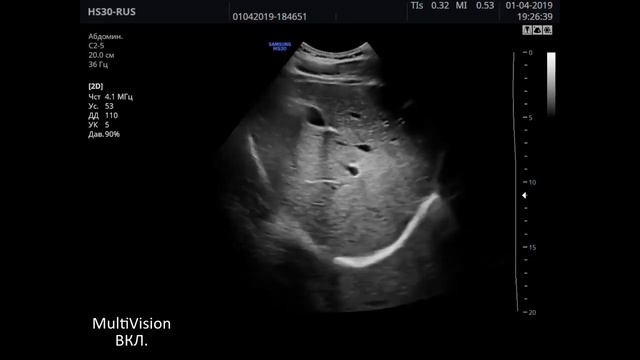

Samsung HS40, он же Samsung Medison HS40 - стационарный ультразвуковой аппарат высокого класса, который знают, пожалуй, все врачи ультразвуковой диагностики. Популярный в своем классе южнокорейский УЗИ аппарат может похвастаться своей универсальностью, превосходной разрешающей способностью, новейшими технологиями визуализации и постобработки ультразвукового изображения. УЗИ аппарат Samsung HS40 легко справляется с оценкой эластичности ткани, трехмерным сканированием объемными датчиками в реальном времени (3D), а также 4D/5D сканированием. УЗИ прибор имеет набор опций для кардиологических исследований, программы для измерений в акушерстве и гинекологии, инновационные технологии и режимы автоматической настройки изображения, что делает HS40 отличным решением для многопрофильных и специализированных медицинских центров. В обзоре ультразвукового аппарата Samsung HS40 клинический специалист компании MEDLIGA Константин Князев расскажет об эргономике прибора, базовых настройках Samsung HS40, для каких исследований подойдет аппарат, а также покажет качество визуализации на примере исследования реального пациента. Samsung HS40 на сайте компании MEDLIGA - https://medliga.ru/products/uzi-apparat-samsung-hs40?utm_source=smm&utm_medium=rutube&utm_campaign=video&utm_content=obzor-knyazev-hs40&rs=smm_rutube_video_obzor-knyazev-hs40 По вопросам медицинского оборудования пишите нам и звоните по тел.: 8 (800) 550-39-27, поможем с выбором необходимой медицинской техники под ваши задачи и бюджет. Подписывайтесь на канал Rutube - https://rutube.ru/channel/26510250/ Вконтакте - https://vk.com/med.liga Телеграм - https://t.me/med_liga 00:05 - Вступление. 00:34 - Направленность исследований УЗИ прибора. 01:03 - Корпус прибора и панель управления. 01:37 - Позиционирование монитора. 01:55 - Датчики Samsung HS40 и разъемы для датчиков. 02:16 - Визуализация. Автоматическая настройка изображений. 02:29 - Структура щитовидной железы. 02:50 - Панорамное сканирование (Panoramic). 02:59 - Визуализация молочной железы. 03:08 - Оценка эластичности ткани Elastoscan. 03:17 - Исследование периферических сосудов. 03:28 - Функция автоматического измерения комплекса интима-медиа (Auto-IMT). 03:40 - Цветная допплерография на Samsung HS40. Спектральный допплер. 03:59 - Исследование конвексным датчиком. Органы брюшной полости. 04:15 - Печень и воротная вена. 04:30 - Визуализация желчного пузыря. 04:42 - Визуализация почки. 05:00 - Исследование органов малого таза на Samsung HS40. 05:35 - Эхокардиография на Samsung HS40. 05:53 - Тканевая цветовая допплерография (TDI). 06:25 - Кому подойдет УЗИ аппарат Samsung HS40. #samsung #medliga #узи #ultrasound